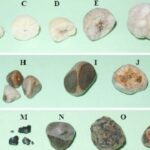

Batu empedu memiliki tingkat keparahan berdasarkan ukuran batu dan penyumbatan pada saluran empedu. Mengenali stadium batu empedu sejak dini penting untuk mencegah nyeri hebat dan komplikasi serius.

Stadium awal: Batu empedu berukuran < 5 mm, sering tanpa gejala dan ditemukan secara tidak sengaja saat pemeriksaan.

Stadium ringan: Batu empedu berukuran 5–7 mm, muncul nyeri ringan di perut kanan atas, perut terasa kembung atau tidak nyaman.

Stadium sedang: Batu empedu berukuran 7–10 mm, menyebabkan nyeri hebat setelah mengonsumsi makanan berlemak, disertai mual dan muntah.

Stadium berat: Batu empedu berukuran ≥ 10 mm, berisiko menyumbat saluran empedu, dapat disertai demam, serta kulit dan mata menguning (ikterus).

Semakin tinggi stadium batu empedu, semakin berat gejalanya. Jangan tunda penanganan agar batu empedu tidak semakin parah dan berisiko komplikasi.